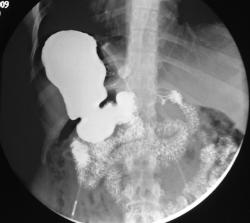

Предлагаю ознакомиться с этими картинками; они многое пояснят! Но, в моём наблюдении не просто ятрогения, но есть осложнение, постарайтесь логически догадаться какое.

Получается муфта соскользнула с желудка и уперлась в диафрагму, тем самым наверное поддавив абдоминальный сегмент пищевода

???? А вернее была наложено выше!

Да, в настоящее время считается одним из самых эффективных методов. Показан пациентам с 3ей и 4ой степенью ожирения. Принцип простой; на проксимальный сегмент желудка накидывается манжетка; которая как петля захватывает желудок; как бы создавая искусственный стеноз на уровне петли и формируя из верхней части маленький резервуар. Этот резервуар быстро наполняется малым количеством пищи; и пациент чувствует насыщение. Люди за год теряют до 30-40 кг. При помощи зонда и имплантированного под кожу аппликатора с физиологическим раствором, можно контролировать степень сужения (диаметра петли). Одно из самых распространённых осложнений при таких процедурах - синдром "соскальзывания" петли. Slipped gastric band syndrome.